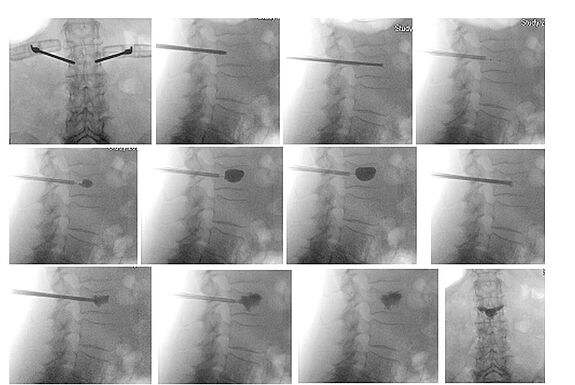

Für eine genaue Absicherung werden spezielle Maßnahmen vorgenommen, bei denen Injektionen eines Lokalanästhetikums (Betäubungsmittels) direkt in den Spaltraum des Gelenkes vorgenommen werden. Führt die Injektion zu einer deutlichen Abnahme der Schmerzen im Iliosakralgelenk (mehr als 50 % Schmerzlinderung) für eine Dauer von ein oder zwei Stunden nach der Injektion, gilt der Test als positiv und damit als Bestätigung der Diagnose.

Als weitere Entwicklung zur Operation am Kreuzbein-Darmbein-Gelenk (ISG) werden Implantate eingesetzt. Die OP erfolgt unter Vollnarkose und Röntgen-Kontrolle. Der Eingriff wird über einen 2-3 cm großen Hauteinschnitt vorgenommen. Mittels eines kanülierten Einführsystems in das Iliosakralgelenk (ISG) bringen wir die Titan-Implantate ein. Diese minimalinvasive chirurgische Fusion des Iliosakralgelenks bringt viele Vorteile für betroffene Patienten:

Eine Infiltrationstherapie unter Röntgenkontrolle mit lokalen Betäubungsmitteln und Kortisonlösung kann zu einer lang anhaltenden Besserung führen.

Bei der Vertebroplastie handelt es sich um einen Eingriff, bei dem unser Operateur unter geführter Bildgebung minimal-invasiv eine Nadel in den Wirbelkörper einführt und Knochen-Zement injiziert. Dieser Zement härtet schnell aus, stabilisiert die Fraktur, was zum Erhalt der neurologischen Funktionen führt.

Die Kyphoplastie ist ein sehr ähnliches Verfahren. Hierbei verwenden wir einen Ballon, um den Wirbelkörper zu erweitern, bevor wir den Zement injizieren.